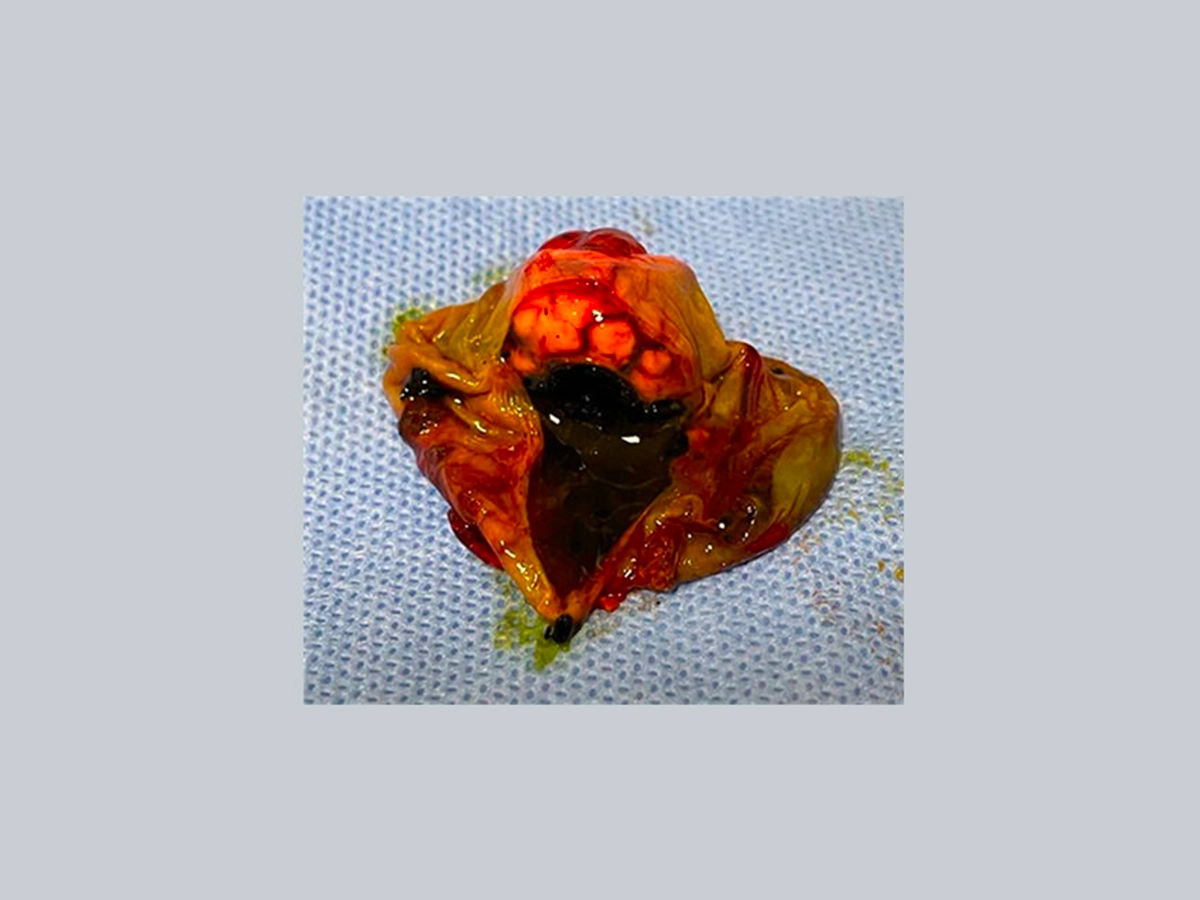

The macroscopic appearance of the neoformation is visible in the figure. The anatomopathological report shows a densely cellular, nondemarcated, noncapsular neoplasm with fibrovascular infiltrating growth.

Following ultrasound examination and histological examination, a neuroendocrine neoplasm of the gallbladder (carcinoid) was diagnosed. The patient therefore underwent cholecystectomy.